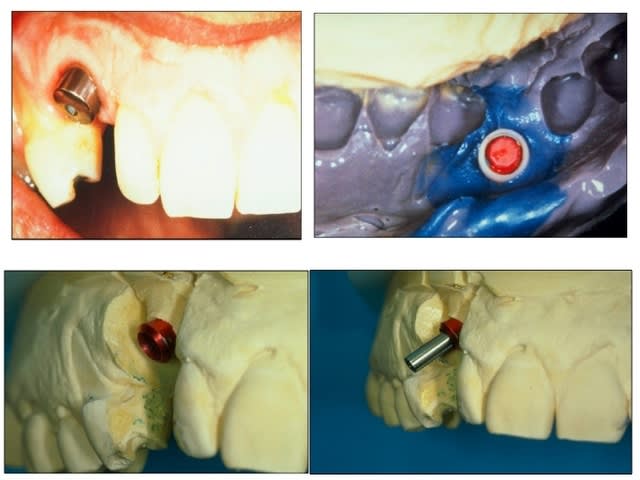

rvg fin novembre du bricolage comme tu le souhaitais.

dis tu me montre la tienne...

en ragardant le sujet vis cassée je vous donne des nouvelles de l'implant col cassé deux ans après et du petit bricolage généré dessus.

nous avons réalisé une armature sur la barre avec un petit fraisage et scellé le tout.

comme j'ai la chance que les patients fassent le suivi

rvg en 2011

pseudo réossification autour de mon bricolage si on fait attention faut dire que c'est un beau cône morse (!)